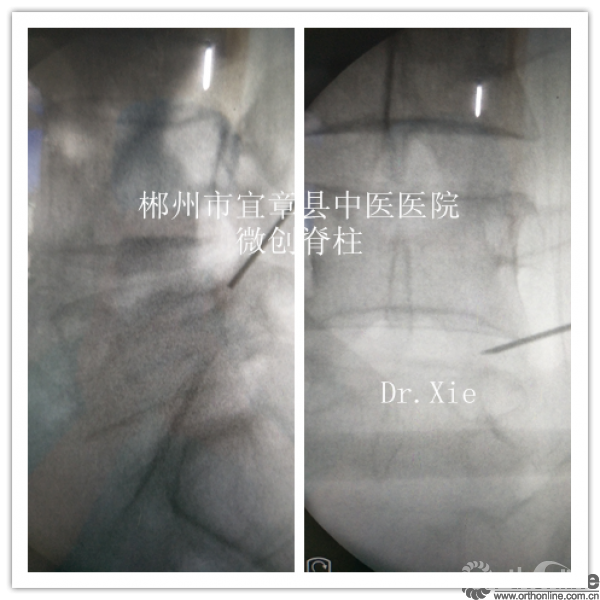

术中情况

术前体表做好标记

穿刺起点:上关节突基底部

终点:下位椎体椎弓根上部

成型部位:关节突基底部及椎弓根上缘,对于向下游离及神经根管狭窄的患者尤为适合。

置管及成型时候正侧位情况